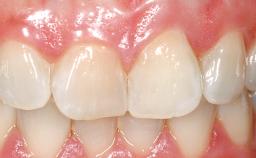

A 39-year-old male patient presented with a chief complaint of discomfort and gingival discoloration around his maxillary left central incisor. He was in good general health and was a non-smoker. His past dental history was significant because of the traumatic fracture of tooth 21 in a sporting accident at age 13. Initial dental treatment included endodontic therapy and a full-coverage restoration. The patient became symptomatic 5 years later, when structural failure of the tooth resulted in the dislodgment of the crown. Endodontic retreatment, apical surgery, and post-and-core restoration were performed.